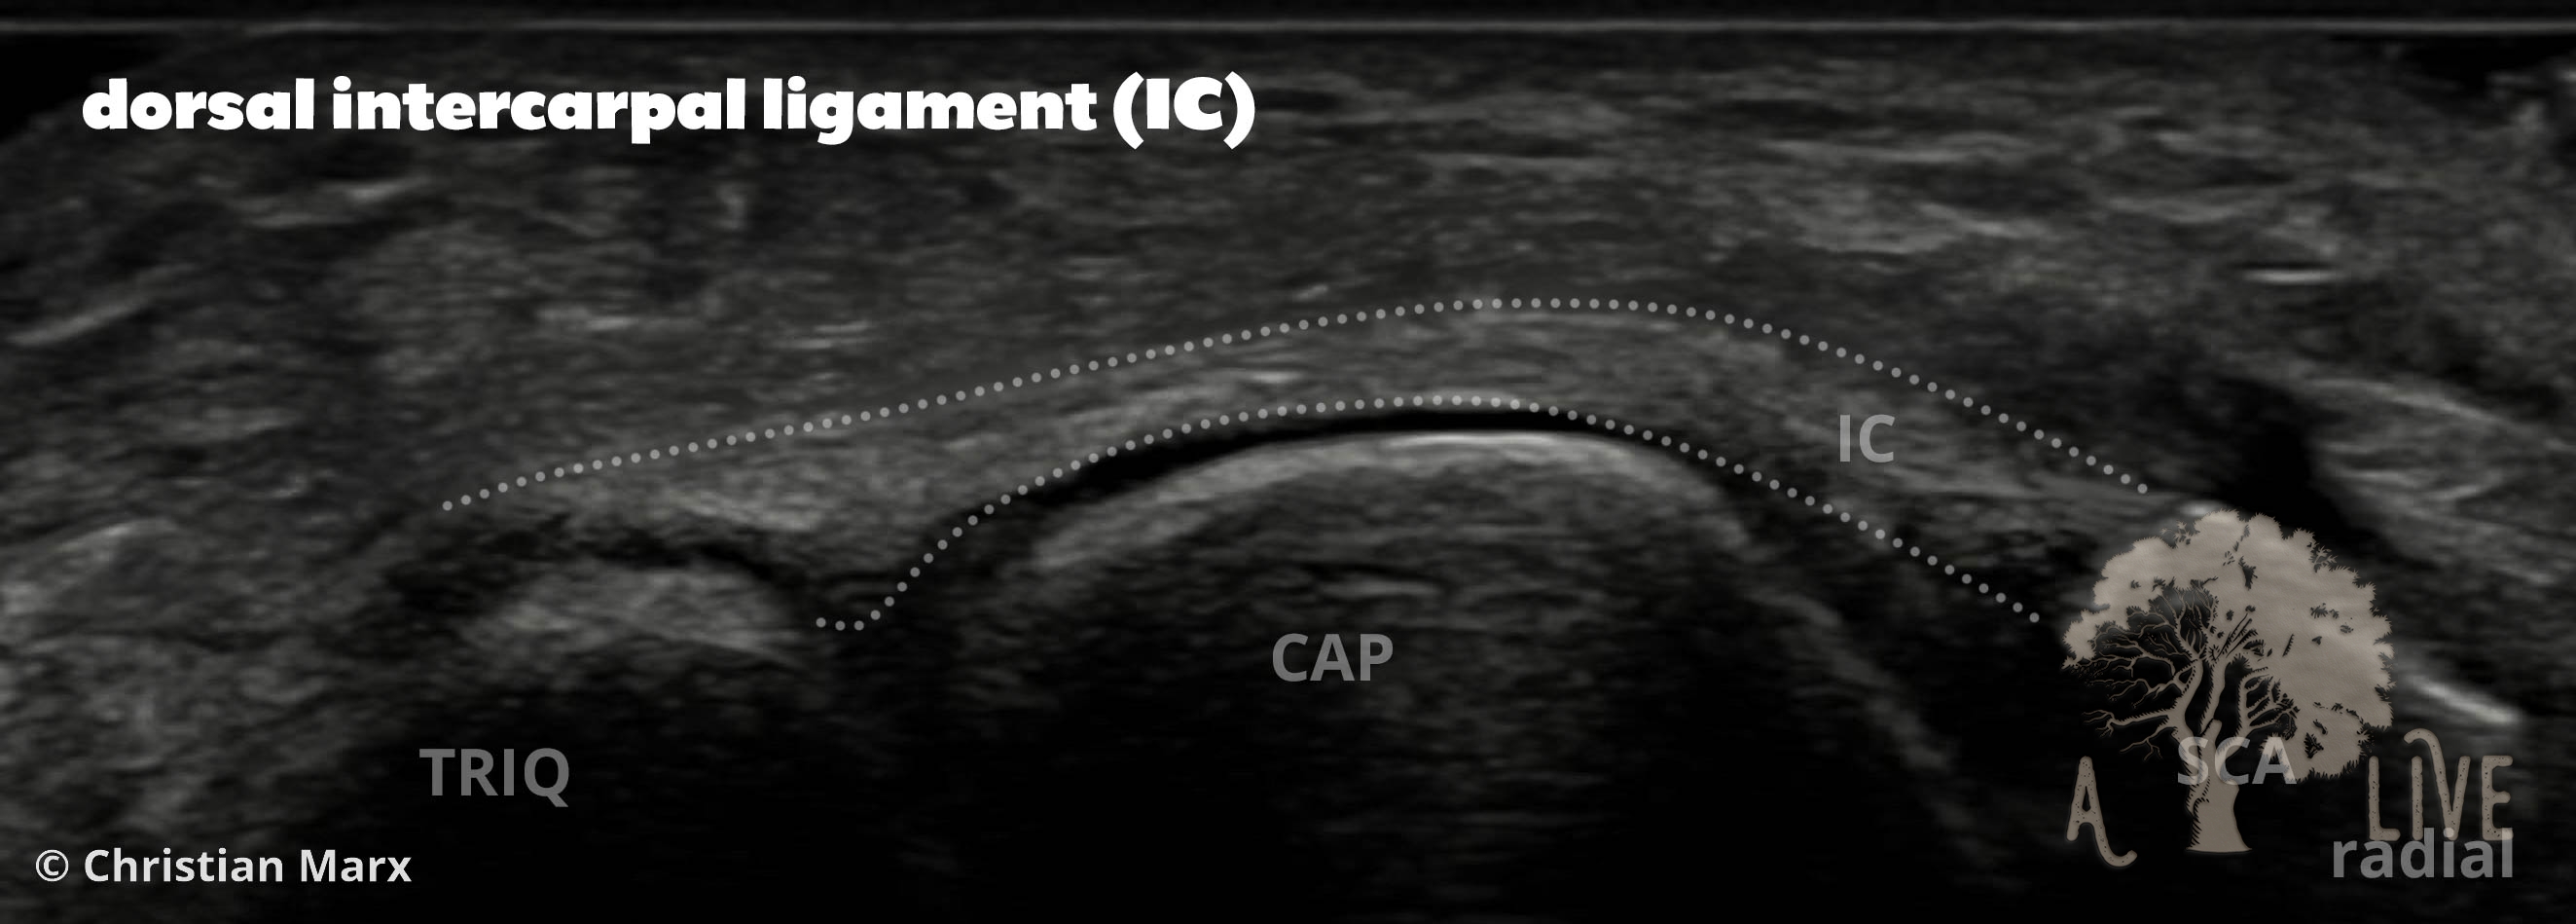

carpal ligaments